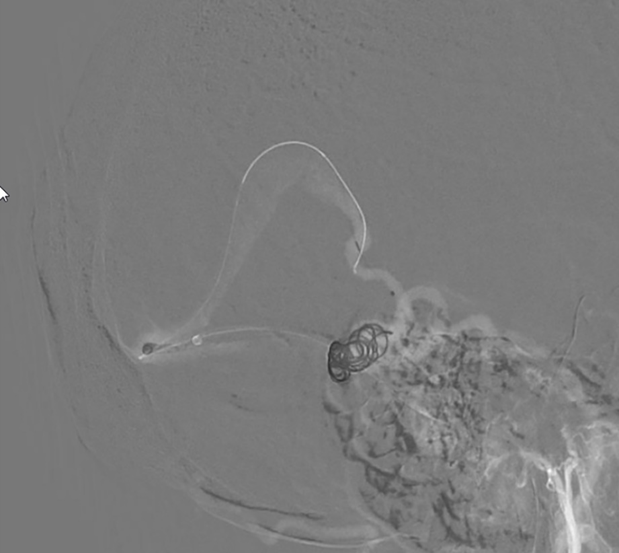

ជំនួសឱ្យការវះកាត់ខួរក្បាលបើកចំហរតាបែបបុរាណ វេជ្ជបណ្ឌិតបានជ្រើសរើសសម្រាប់នីតិវិធីអន្តរាគមន៍ផ្នែកសរសៃឈាមខាងក្នុងEndovascular ។ នេះគឺជាវិធីព្យាបាលកម្រិតខ្ពស់ទំនើប និងរាតត្បាតតិចតួចដែលត្រូវបានគេស្គាល់ពីប្រសិទ្ធភាពខ្ពស់របស់វា ប៉ុន្តែទាមទារភាពជាក់លាក់ និងជំនាញច្បាស់លាស់។ អ្នកជំងឺត្រូវបានផ្ទេរភ្លាមៗទៅកាន់បន្ទប់ឆ្លុះសរសៃឈាម ជាកន្លែងដែលលោកវេជ្ជបណ្ឌិត Huynh Huu Danh អនុវត្តនីតិវិធីផ្ទាល់ដោយមានការគាំទ្រពីប្រព័ន្ធ Digital Subtraction Angiography (DSA)។

តាមរយៈស្នាមវះតូចមួយនៅភ្លៅ លោកវេជ្ជបណ្ឌិត Danh បានធ្វើអន្តរាគមន៍ដោយប្រុងប្រយ័ត្ននូវបំពង់ និងខ្សែមីក្រូ-មគ្គុទ្ទេសក៍តាមរយៈសរសៃវ៉ែន ដើម្បីឈានទៅដល់កន្លែងដាច់សរសៃឈាមក្នុងខួរក្បាល។ សរុបចំនួន 12 ខ្សែ (លួសដែក) ត្រូវបានដាក់នៅខាងក្នុងរន្ធសរសៃឈាមដើម្បី “បំណះ” តំបន់ដែលខូចនិងរារាំងលំហូរឈាមតាមរយៈការធ្លាយ។